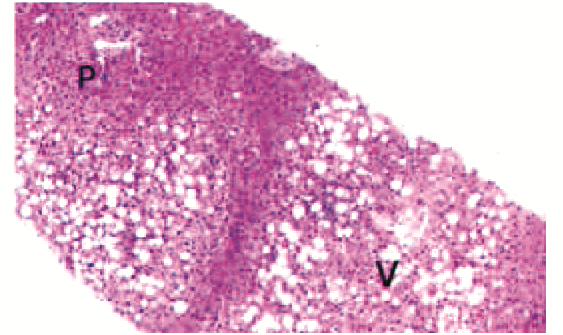

非酒精性脂肪性肝病儿童肝组织病理特征分析

刘敏, 陈卫坚, 周峥珍, 覃小梅, 文容, 姜楠, 匡林芝, 郑台青, 张丽琼, 李双杰

2023, 39(5): 1144-1149. DOI: 10.3969/j.issn.1001-5256.2023.05.021

摘要(861) HTML (394) PDF (3065KB)(80)

摘要: